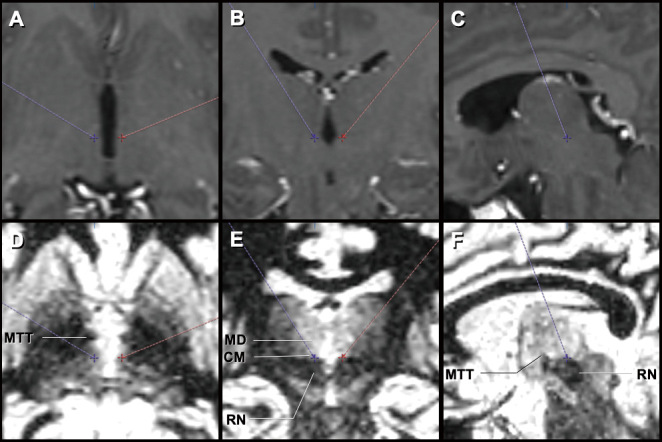

图雷特综合征(TS)是一种以抽搐为特征的发育性神经精神疾病。对于药物和行为疗法难治的严重病例,脑深部刺激(DBS)可能是一种治疗选择。在本研究中,我们回顾了用于重度 TS 患者 DBS 的手术技术及其临床效果,并根据我们的经验和文献,试图确定最佳手术方法和当前存在的问题。共有 14 名患者参与了这项研究,其中男性 13 人,女性 1 人,他们都接受了丘脑中枢 DBS 治疗,平均随访时间为(2.3 ± 1.0)年。耶鲁全球抽搐严重程度量表(Yale Global Tic Severity Scale)的平均严重程度评分从基线时的(41.4 ± 7.0)明显降低到 6 个月时(19.8 ± 11.4)(P = 0.01)和最后一次随访时(12.7 ± 6.2)(P < 0.01)。此外,耶鲁全球抽搐严重程度量表(Yale Global Tic Severity Scale)的平均障碍评分从基线时的 47.1 ± 4.7 显著改善到 6 个月时的 23.1 ± 11.1(P < 0.01)和最后一次随访时的 7.6 ± 2.9(P < 0.01)。然而,术后持续监测存在问题(三例患者失去了随访机会),并且出现了与手术相关的不良事件,包括导线错位和因严重自伤性抽搐导致的延迟性脑内出血各一例。这项研究的目的不仅在于强调 DBS 治疗 TS 的临床疗效,还在于强调其面临的挑战。临床医生应了解大脑的三维解剖结构,这样才能进行精确的手术操作,避免不良事件的发生,实现 DBS 治疗 TS 的良好疗效。

Tourette syndrome (TS) is a developmental neuropsychiatric disorder that is characterized by tic movements. Deep brain stimulation (DBS) may be a treatment option for severe cases refractory to medical and behavioral therapies. In this study, we reviewed the surgical techniques used for DBS in patients with severe TS and its clinical outcomes and sought to determine the optimal surgical procedure and current issues based on our experience and the literature. A total of 14 patients, consisting of 13 men and 1 woman, who underwent centromedian thalamic DBS and were followed up for a mean duration of 2.3 ± 1.0 years, participated in this study. The mean Yale Global Tic Severity Scale severity score significantly improved from 41.4 ± 7.0 at baseline to 19.8 ± 11.4 at 6 months (P = 0.01) and 12.7 ± 6.2 at the last follow-up (P < 0.01). Moreover, the mean Yale Global Tic Severity Scale impairment score significantly improved from 47.1 ± 4.7 at baseline to 23.1 ± 11.1 at 6 months (P < 0.01) and 7.6 ± 2.9 at the last follow-up (P < 0.01). However, there were problems with continuous postoperative monitoring (three cases were lost to follow-up) and surgery-related adverse events, including one case each of lead misplacement and a delayed intracerebral hemorrhage due to severe self-injurious tics. This study aimed to highlight not only the clinical efficacy of DBS for TS but also its challenges. Clinicians should understand the three-dimensional brain anatomy so that they can perform precise surgical procedures, avoid adverse events, and achieve favorable outcomes of DBS for TS.